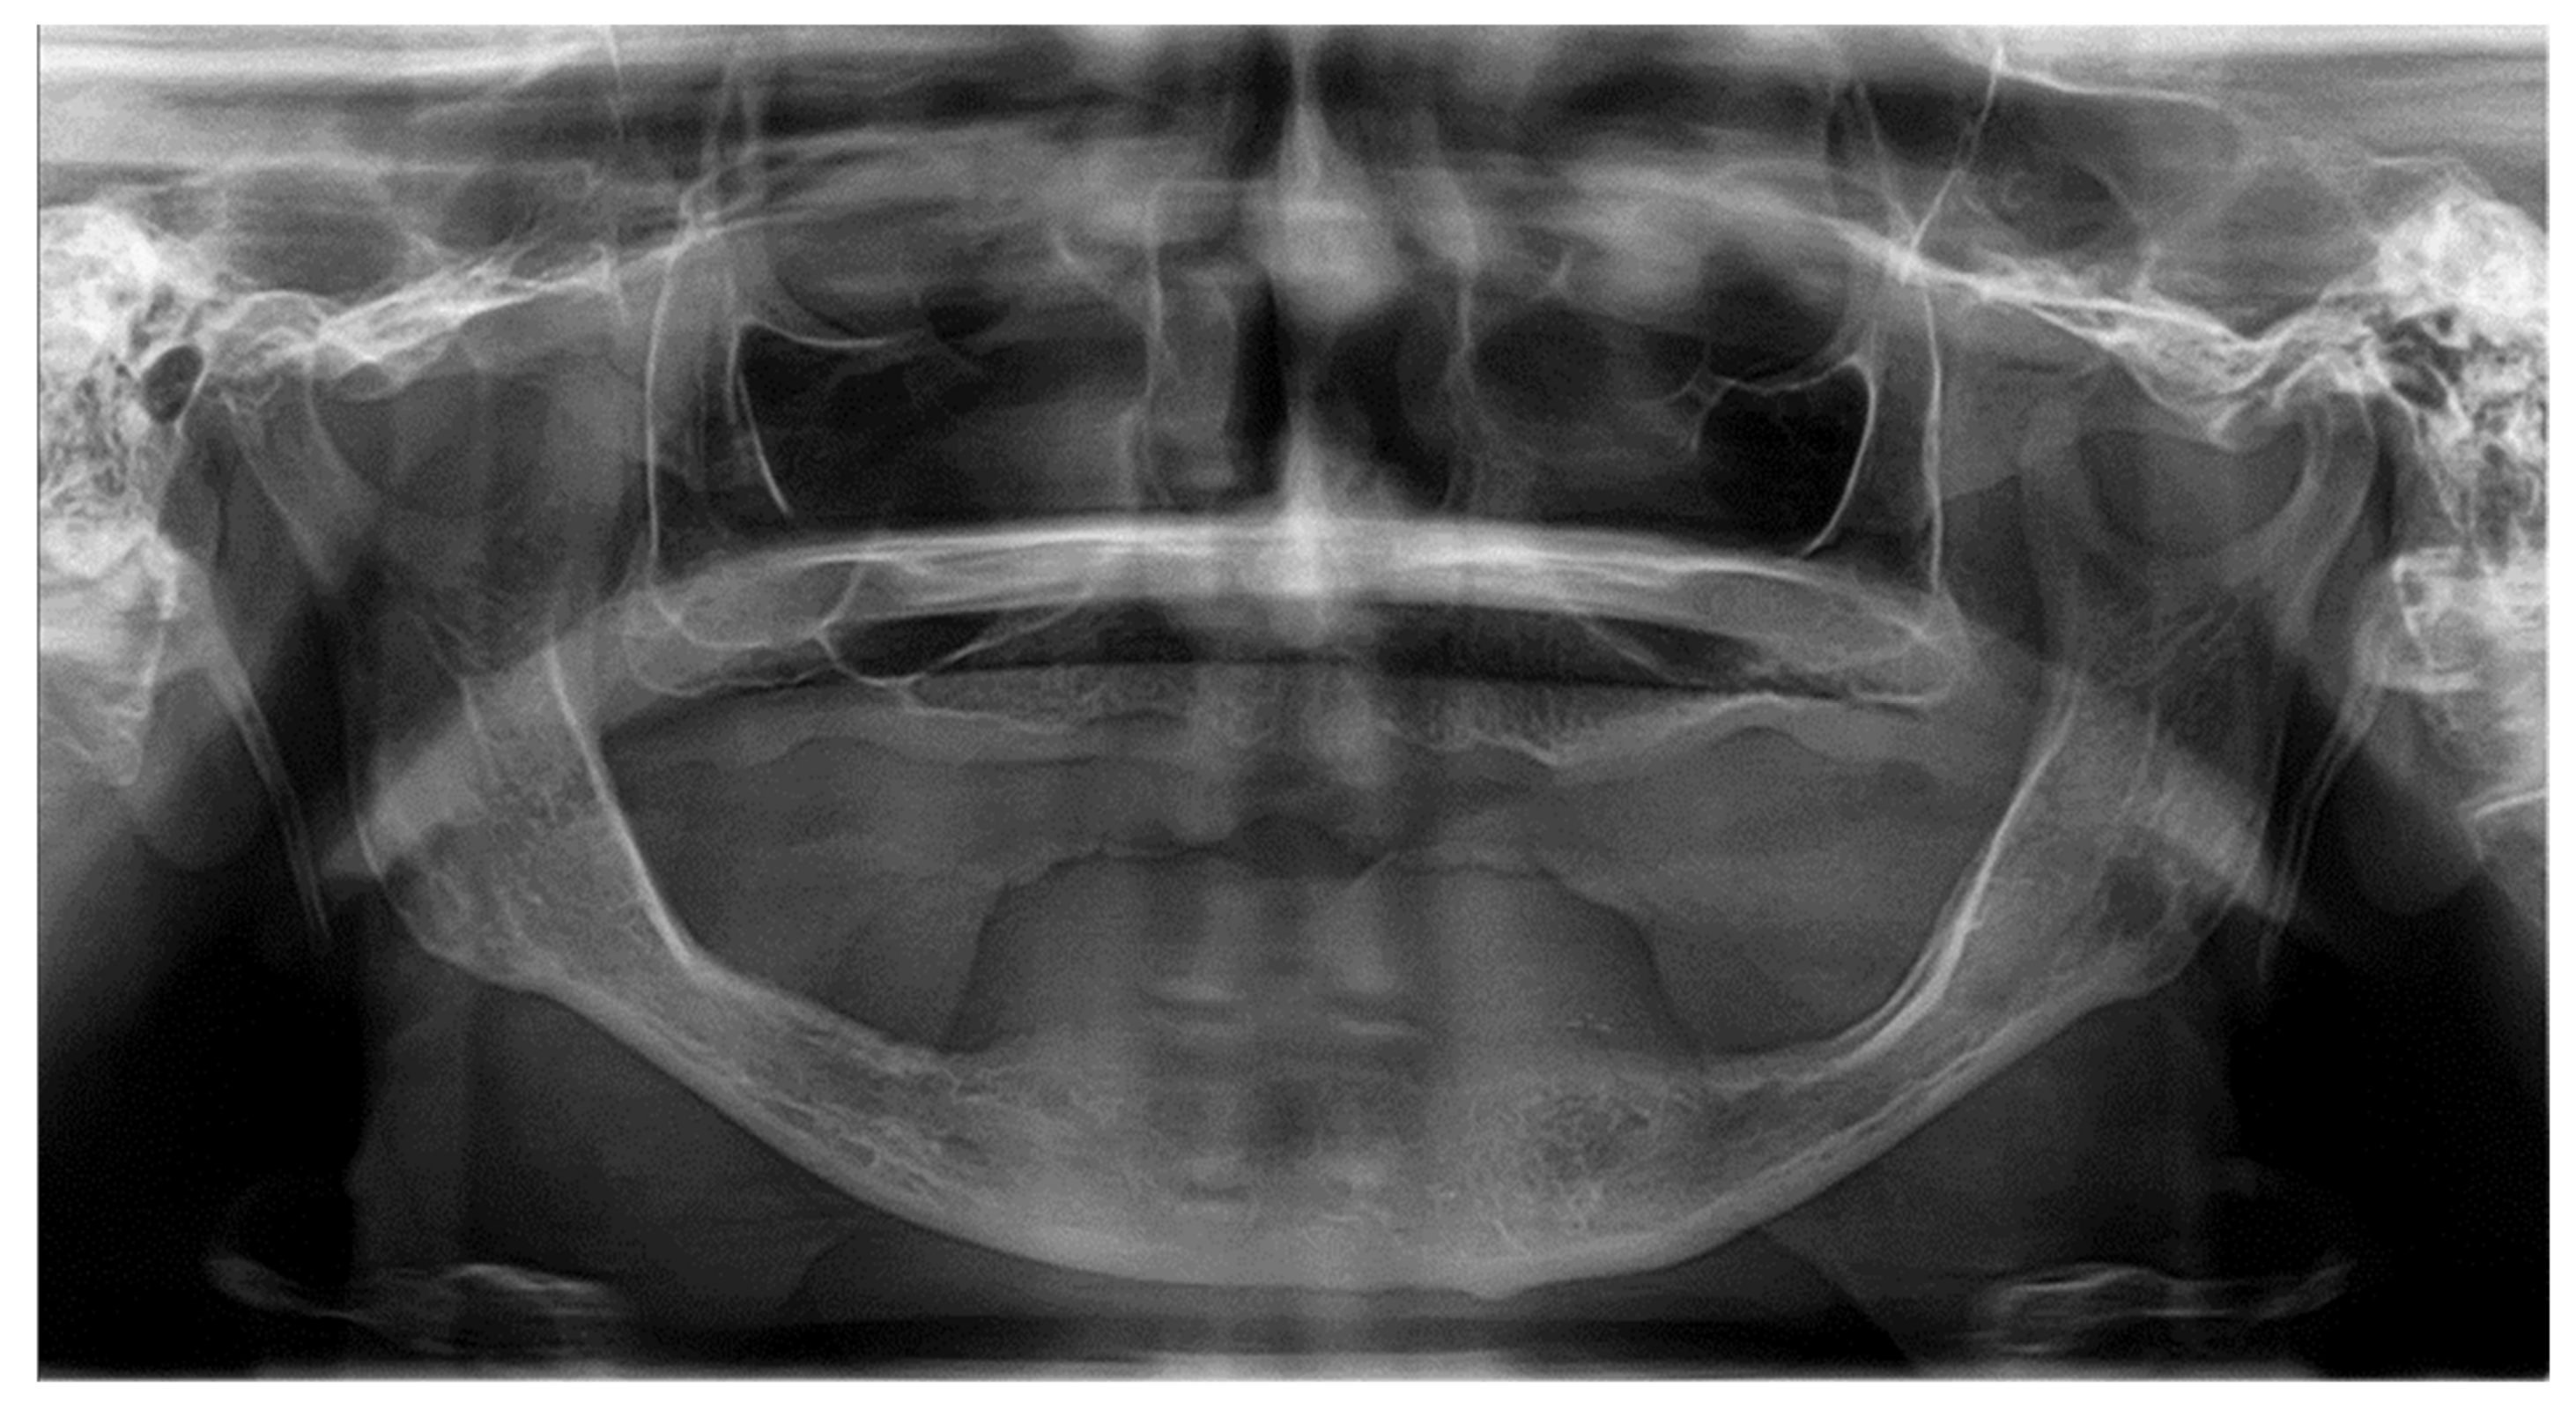

2.4. Description of the Clinical Case Vignettes